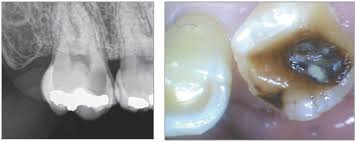

- 심한 충치: 충치가 깊어져 신경까지 도달한 경우

- 진단 및 엑스레이: 감염 범위 확인